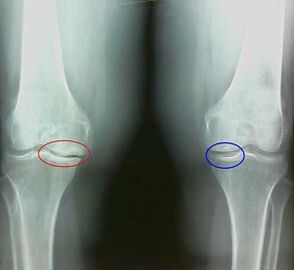

For example, what is the difference between arthritis and knee arthrosis?With arthritis, the synovial sheath of the joint tissue appears.This leads to an increase in the temperature in the joint.

The joint swells, a constant pain syndrome develops, intensifying during movement.With arthrosis, pain occurs only after physical activity, you can hear a characteristic crisis or clicks in the joint, gradually the joint is deformed and loses mobility.